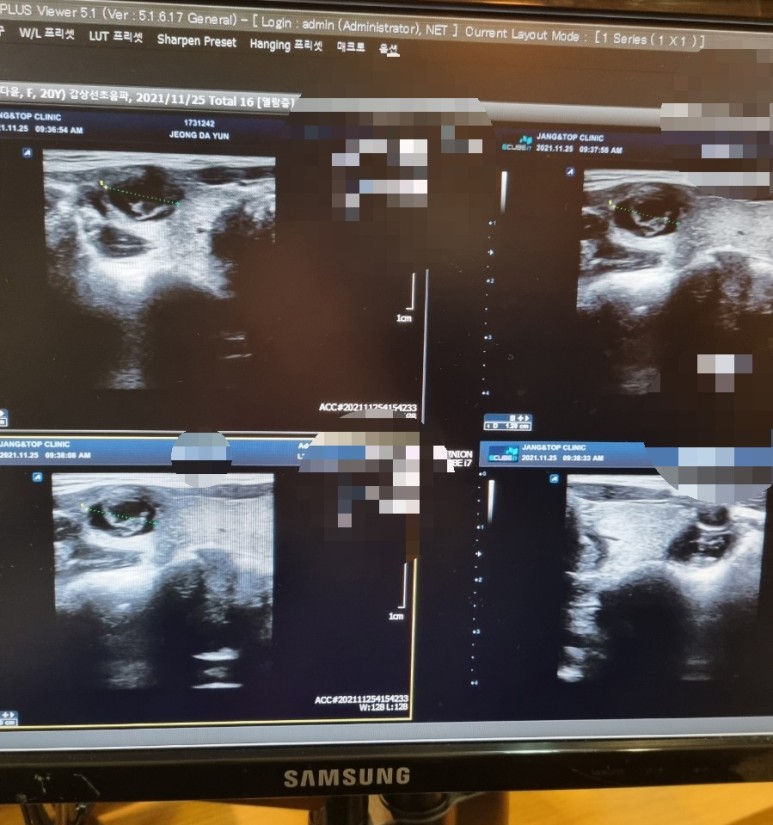

검사 결과 갑상선 결절이 있고 갑상선 맨 윗부분에 위치한

송도에 있는 남문석내과의원에서 초음파를 받았다. 내분비내과 전분병원이다.

생각보다 사이즈가 컸어 ㅠㅠ 무려 1.5cm ….그동안 어떻게 몰랐을까 하고 의아했다

가로로 길고, 종양의 안쪽은 완전히 지쳐 있는 것, 주변 세포와 경계가 분명한 것 등 종양의 형태는 거의 좋았다.

그런데!! 목 근육 조직과의 경계가 조금 불분명하다면서 조직검사를 하는 것이 좋겠다고 하셨어…(암일 가능성이 있다고..)